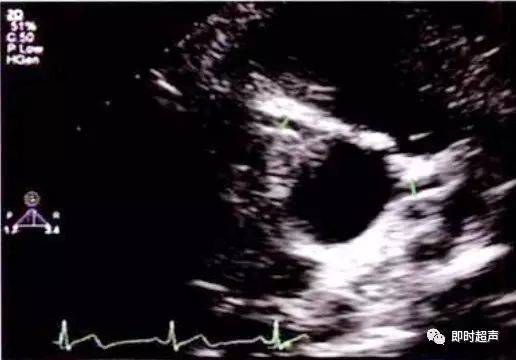

图解二维超声心动图正常值与测量